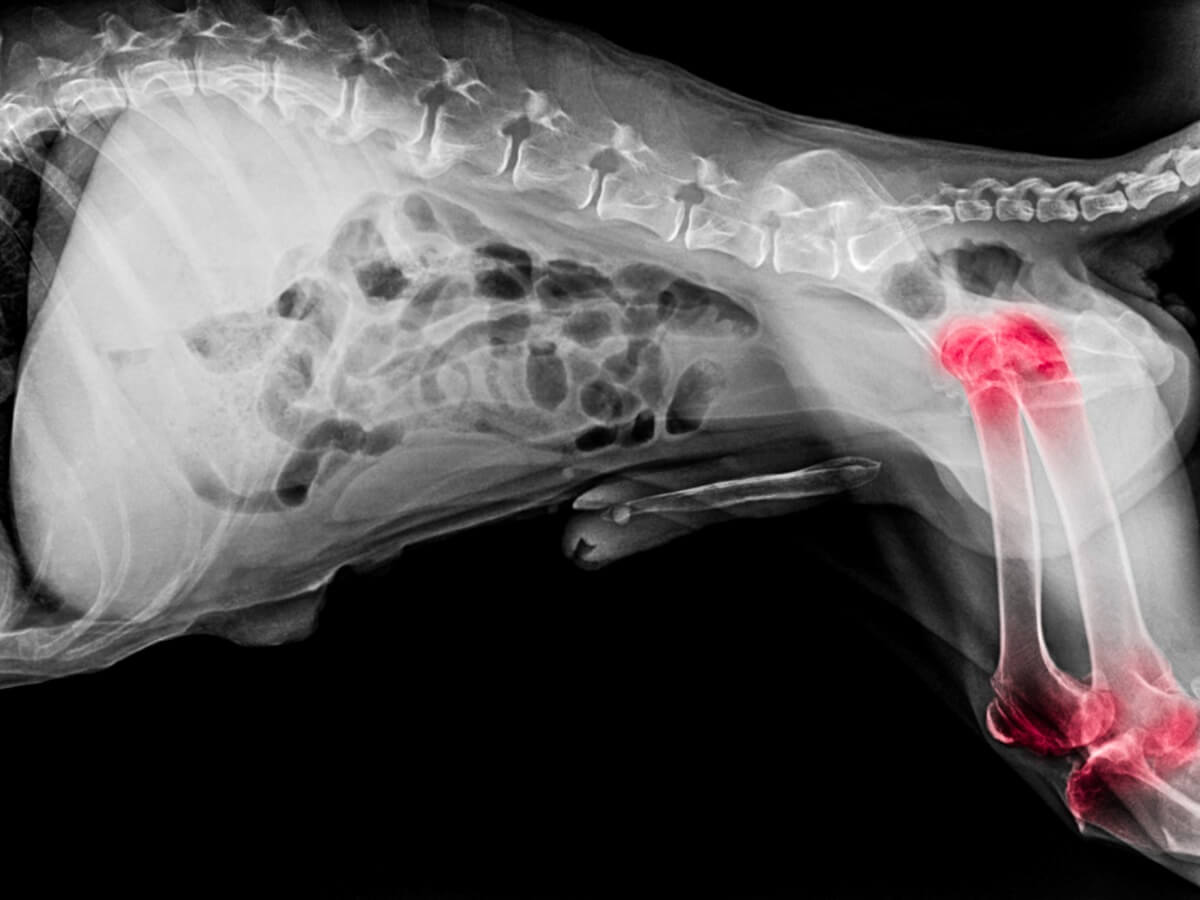

La artritis es un problema articular provocado por la hinchazón y sensibilidad en las articulaciones. Algunos de los síntomas más comunes que se pueden apreciar cuando un perro sufre artritis son los siguientes:

- Inflamación visible en las articulaciones.

- Deformación de las articulaciones.